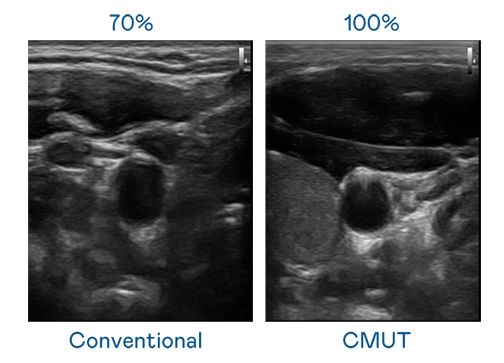

CMUT 技术是一种用电容式微机电元件来产生超音波讯号的技术。与传统 PZT 压电式技术相比,CMUT 频宽增加 30%,更宽频的超音波讯号让影像解析度大幅提升,是实现高影像品质医疗超音波扫描、促进精准医疗发展的关键技术。

大频宽带来超清晰影像

超音波影像的解析度高低,首先取决于探头能发出的讯号频宽。爱游戏体育网页登录 CMUT 可提供高清晰的超音波讯号,提供高频宽、高灵敏度、影像纹理细节更高的超音波影像,协助医护人员缩短影像判读时间及利用精准的医疗影像进行诊断。